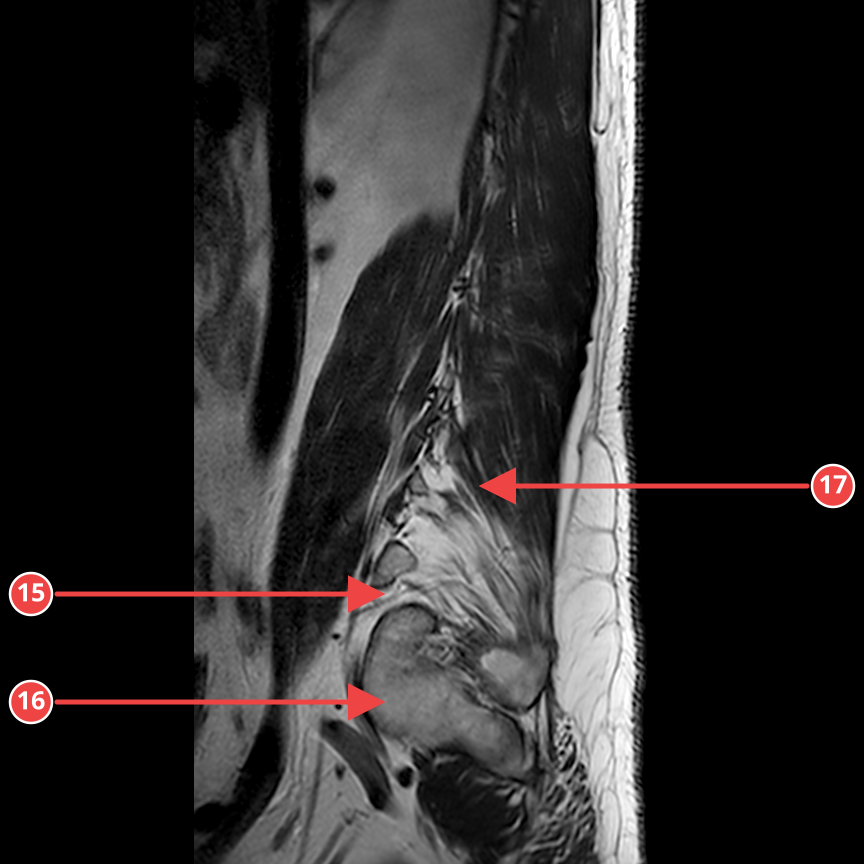

IMG-0002-00018.dcmT2_SAG

Сагиттальная T2-взвешенная последовательность тазобедренного сустава. Определяется небольшое количество жидкости в полости сустава и неоднородность суставного хряща.

Аномалии

- [4] Выпот в полости тазобедренного сустава — medium — Умеренное количество свободной жидкости в полости сустава. уверенность 75%

- [5] Неоднородность суставного хряща — medium — Очаги истончения и неоднородности сигнала хряща в зоне нагрузки. уверенность 60%